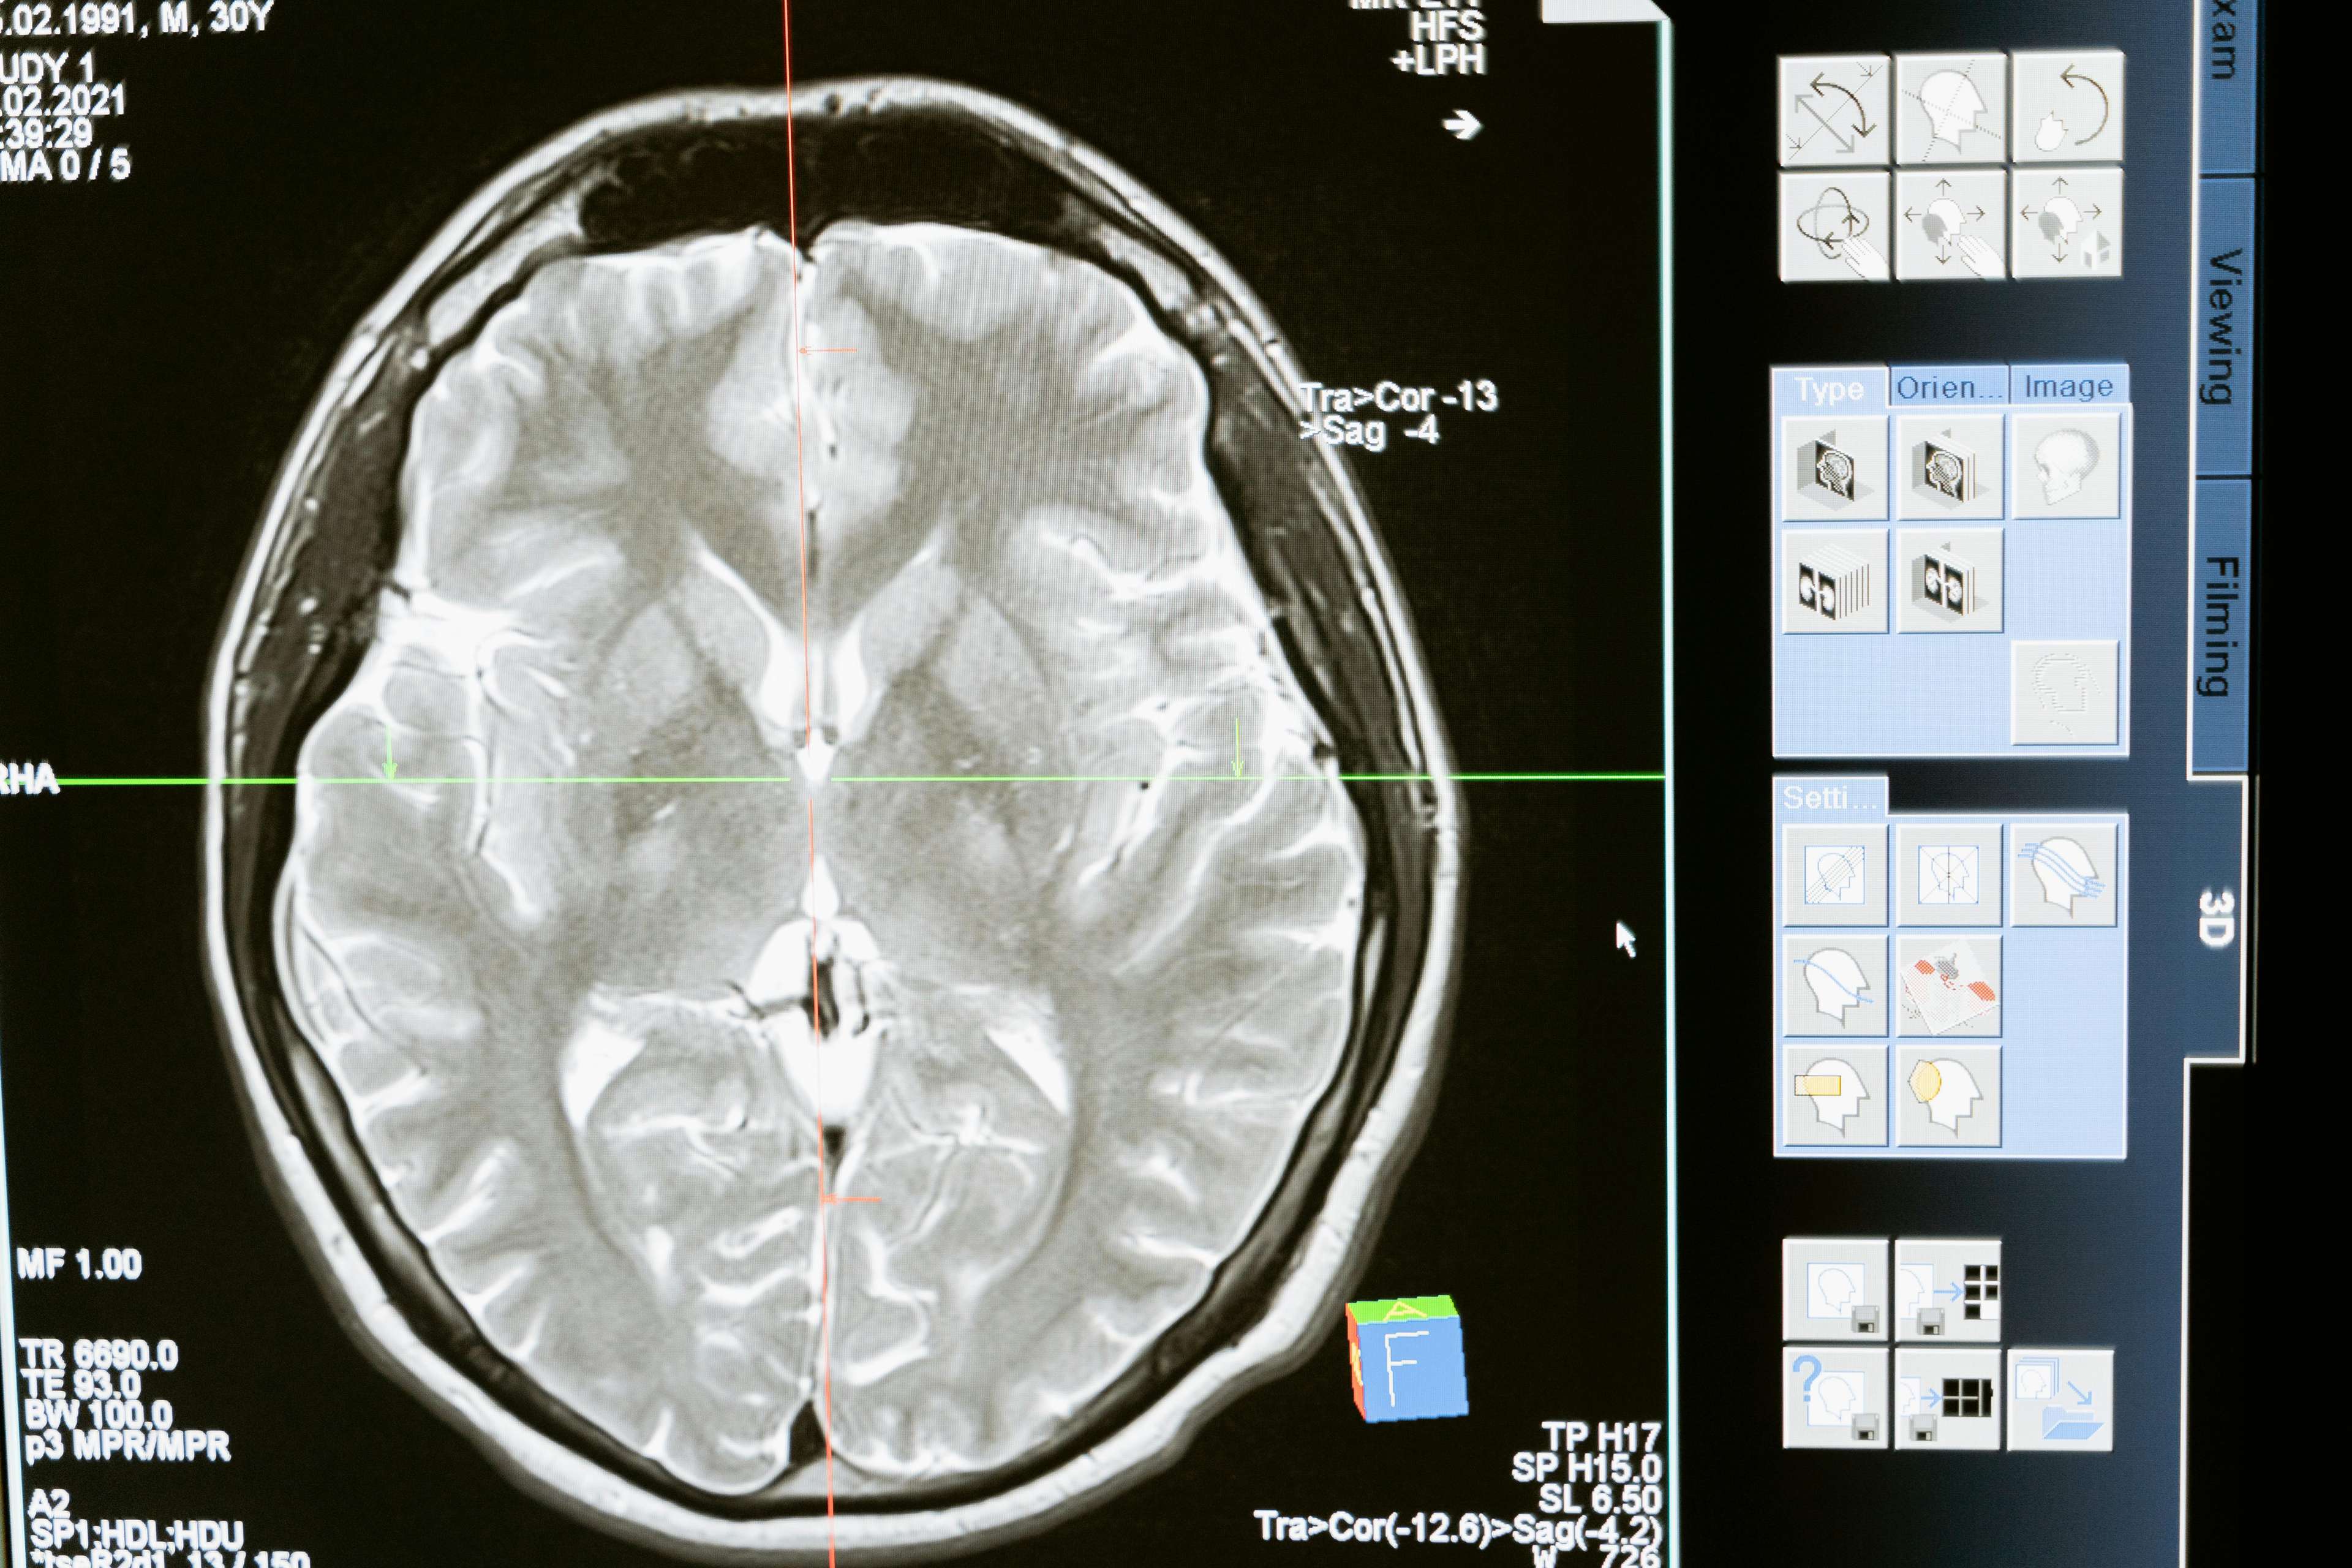

In the 1990s, a breakthrough in medical technology offered new hope for Parkinson's patients. Deep Brain Stimulation, a surgical procedure that involves implanting a device that delivers electrical impulses to specific areas of the brain, has been shown to significantly improve motor function and reduce symptoms. By targeting the areas of the brain responsible for motor control, DBS helps to regulate abnormal brain activity, allowing patients to regain control over their movements.